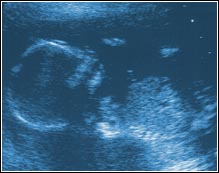

Week Nine. The fetus is now one inch long. Still too

early to determine its sex, but it has eyes, fingers, and toes.

We could see its heart beating and its arms moving!

The little round ball just below its feet is the yolk sac.

Below that is the area in which the placenta will form.